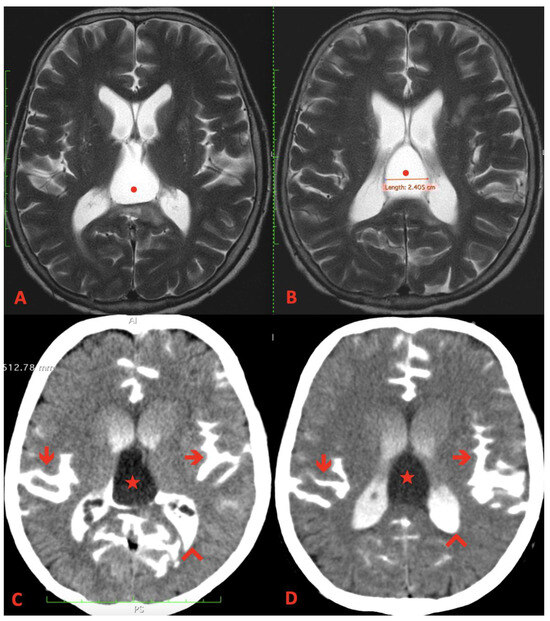

2. Case Report

3.2. Imaging

- T1-Weighted Images: Midline cysts typically appear hypointense (dark) on T1-weighted images.

- T2-Weighted Images: These cysts usually appear hyperintense (bright) on T2-weighted images, reflecting their fluid content.